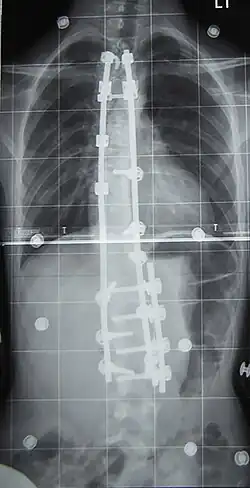

Хирургическое лечение

При неуспехе бескровного консервативного лечения из-за нарушения предписанного режима ношения корсета, плохого качества изготовленного корсета или отказе от него рассматривается операция по установке металлических конструкций и аутотрансплантантов (небольших фрагментов кости таза пациента, превращённых в костную крошку) фиксирующих между собой тела позвонков, называемая «спондилодез» или «fusion»-закрепление(слияние, заваривание).

При оперативном лечении искривлённая часть позвоночника выпрямляется до определённого возможного угла при помощи металлических стержней и шурупов (т. н. транспедикулярных винтов), что ведёт к полному обездвиживанию этих отделов позвоночника. Операция при сколиозе подходит прежде всего для сильных искривлений, которые больше не могут лечиться другими методами. Оперативная фиксация может предотвратить дальнейшую прогрессию и ухудшение состояния.

Оперативный разрез при заднем доступе находится на средней линии туловища и одном из крыльев тазовой кости. Используются различные системы металлических стержней, которые крючками или шурупами (т. н. педикулярными винтами) прикрепляются к позвоночнику и затем изменяют его кривизну на больших участках. Для лучшей стабилизации всей конструкции стержни имеют поперечные соединения (мостики).

После операции теряется подвижность в зафиксированных отделах позвоночника. Это способствует впоследствии сращению тел позвонков в единый костный блок необходимой длины и желаемой геометрии. Недостаток метода состоит в том, что позвоночник на больших участках оказывается обездвижен, и общая подвижность позвоночного аппарата ограничена, что вынуждает пациента менять привычные стереотипы движений. Преимущество метода с костной фиксацией позвоночника от операций без такой костной фиксации в более заметной косметической коррекции формы туловища и в улучшении баланса при ходьбе.